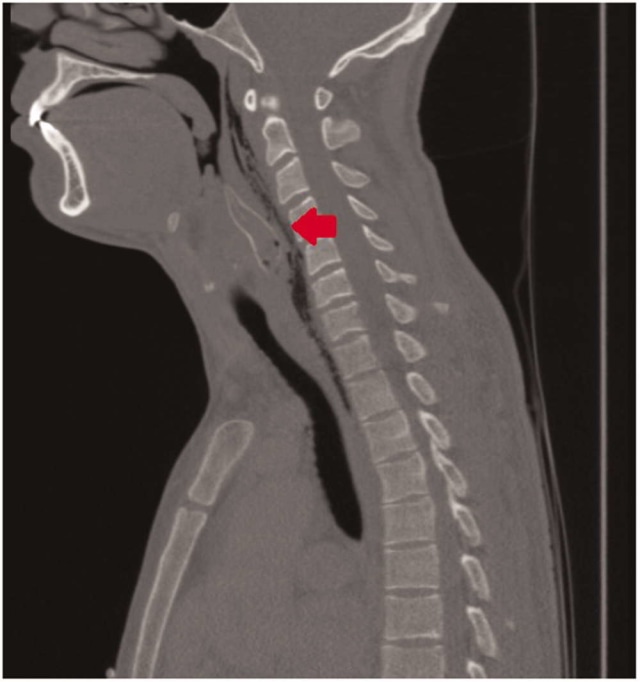

Namun, tidak dengan ikan lele beracun. Saat tahu ia dalam bahaya, ikan itu melakukan perlawanan dengan cara menusukkan duri-durinya ke tenggorakan pria yang menelannya sehingga lele itu tersangkut di tenggorokan. Beruntung, ikan itu berhasil dikeluarkan oleh tim dokter.

Kees Moeliker, kepala Natural History Museum of Rotterdam, yang memeriksa lele ini, menyatakan ikan tersebut memiliki ukuran tubuh yang kecil, hanya sekitar 5 sampai 8 centimeter. Ketika ia diserang, lele akan menggunakan durinya untuk melindungi diri dan duri tersebut bisa mengeluarkan racun.

Ikan tersebut bisa dikeluarkan melalui prosedur operasi beserta sisa-sisa dari ikan yang sudah mati di dalam tenggorokan tersebut, kemudian dijadikan koleksi di Natural History Museum of Rotterdam.